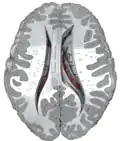

The caudate nuclei are near the center of the brain, sitting astride the thalamus. There is a caudate nucleus in each hemisphere of the brain. Each nucleus is C-shaped, with a wider "head" (caput in Latin) at the front, tapering to a "body" (corpus) and a "tail" (cauda). Sometimes a part of the caudate nucleus is called the "knee" (genu).[6] The caudate head receives its blood supply from the lenticulostriate artery; the tail of the caudate receives its blood supply from the anterior choroidal artery.[7]

The head and body of the caudate nucleus form part of the floor of the anterior horn of the lateral ventricle. The body travels briefly towards the back of the head; the tail then curves back toward the anterior, forming the roof of the inferior horn of the lateral ventricle. This means that a coronal section (on a plane parallel to the face) that cuts through the tail will also cross the body and head of the caudate nucleus.

Caudate nuclei along with other subcortical structures, in glass brain